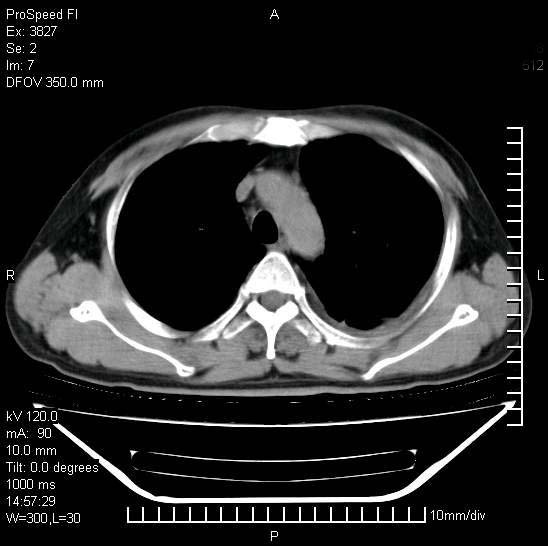

男性,一月前出现右侧肋区疼痛,较剧烈,干咳,无发热,自诉使用抗炎药后缓解,几天前又出现左侧剧烈疼痛,

发热,体温38。9,今天ct,考虑左侧包裹性脓胸,胸腔积液,右上中肺小斑片影,结核/炎症?胸水未见恶性细胞。

左侧肺脓疡,化脓性胸膜炎(脓胸),不支持结核诊断,建议继续抗感染治疗

支持左侧肺脓肿并脓胸,肺内炎症,建议继续抗炎治疗后复查。

脓胸没问题,肺内还可见感染灶,感觉不像是结核性病变.